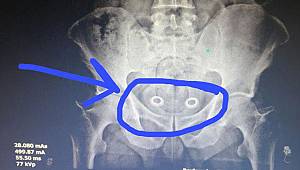

Röntgende ortaya çıktı! Bağırsaklarında gizlemiş...